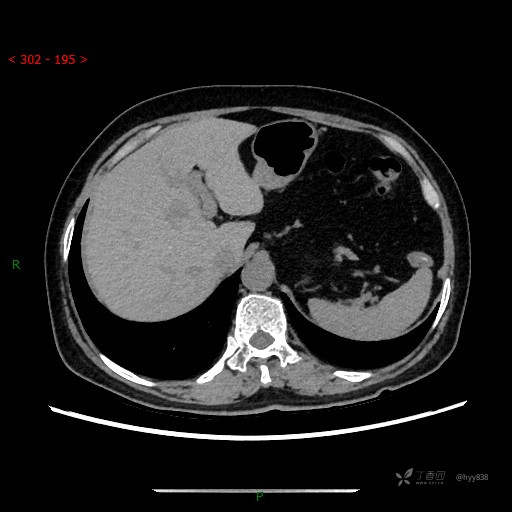

增强动脉期